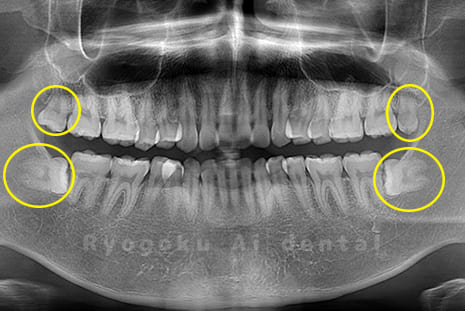

Case04

-

- 原因

- 上顎の親知らず、下顎の水平埋伏の親知らず

- 治療内容

- 上顎の親知らず、下顎の水平埋伏の親知らずを抜歯したケースです。

<リスク・副作用>

手術後は痛み、腫れ、痺れなどの副作用が生じる場合があります。